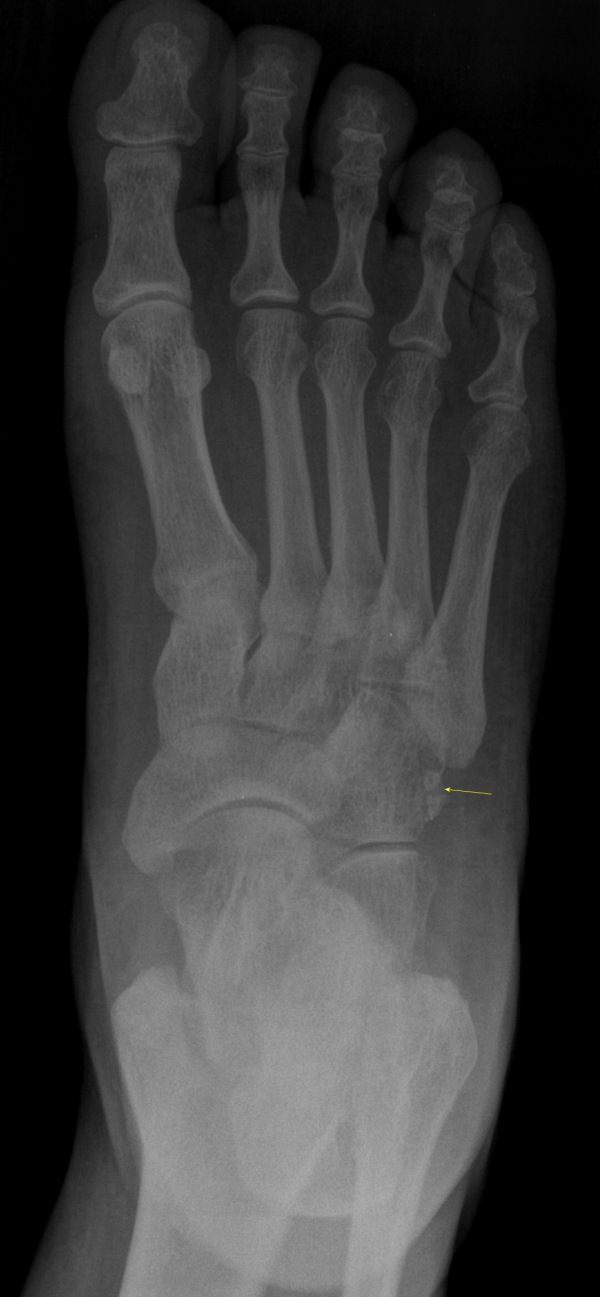

´Ü¼ø¹æ»ç¼±°Ë»ç

ºñ°ñ°ÇÀÇ °ñÀýÀÌ ÃßÁ¤µÇ´Â ¾ç»ó

os peroneum Àº ¾à 30%¿¡¼­ À̺ÐÈ­(bipartiate)¸¦ ´Ü¼ö³¶»ç¼± ÃÔ¿µ¿¡¼­ µÎ Á¶°¢À¸·Î

º¸ÀÌ´Â °æ¿ì °ñÀýÀÎÁö ¾Æ´Ï¸é Á¤»óÀûÀÎ À̺ÐÈ­ÀÎÁö¸¦ °¨º°ÇØ¾ß ÇÑ´Ù.

ÀÌÇÐÀû °Ë»ç»ó ±¹¼ÒÀûÀÎ ¾ÐÅë, ¹æ»ç¼± ÃÔ¿µ¿¡¼­ Á¾ÀÚ»ÀÀÇ Çü»óÀ¸·Î ¾î´À Á¤µµ °¨º°Àº °¡´ÉÇÏÁö¸¸

ÃÊÀ½ÆÄ°Ë»ç¸¦ ½ÃÇàÇÏ¸é º¸´Ù È®½ÇÇÏ°Ô °¨º°Áø´ÜÀÌ °¡´ÉÇÏ´Ù.